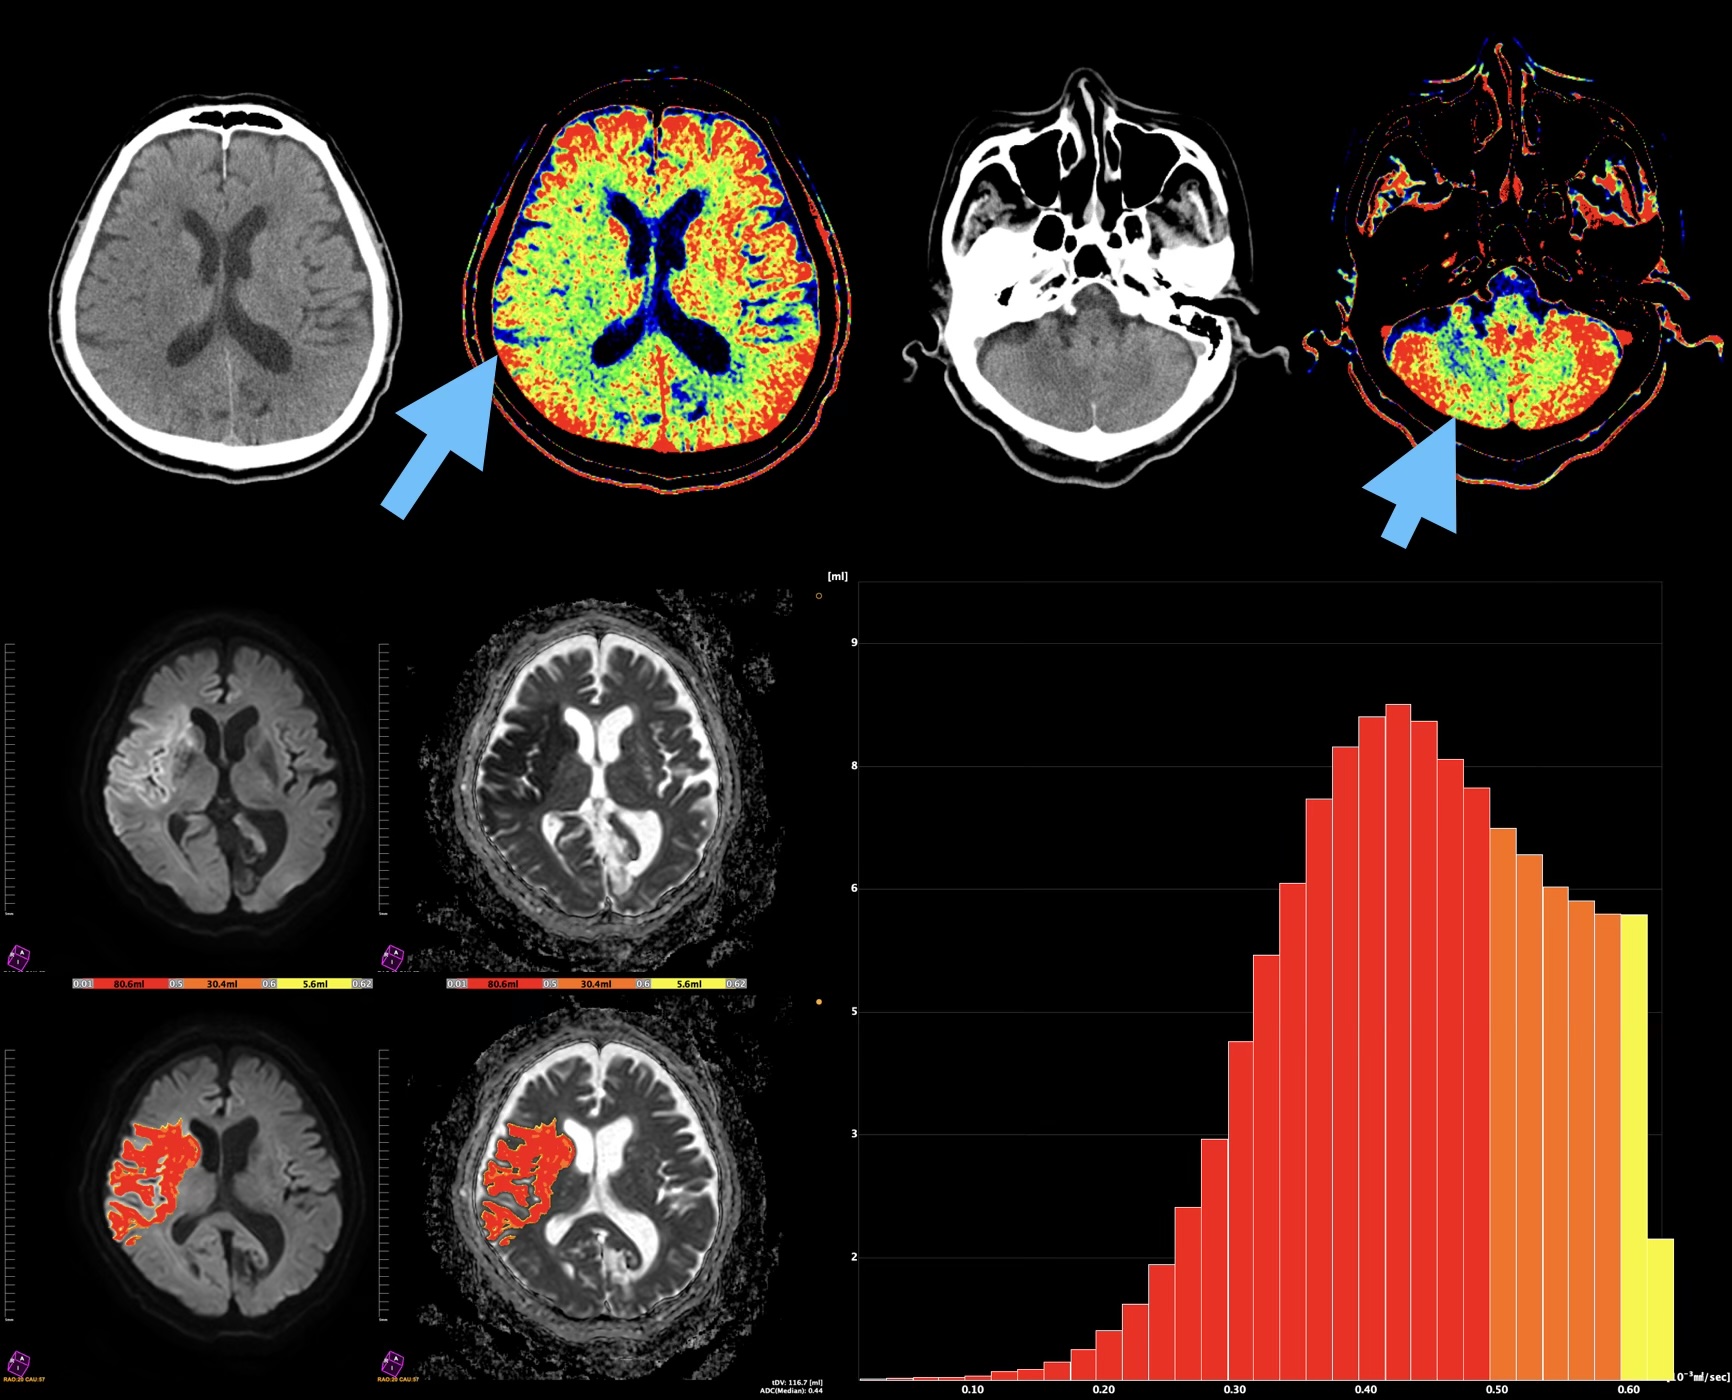

PixSpaceは全身DWIデータの解析プログラム「BD Score」をリリースして来たが、ここ数年は頭部領域でのADCボリューム解析に注目されつつある。ADC値の統計解析によって得られる指標を元に、治療の功奏を予測できる可能性が複数の論文によって示唆されつつある。このような背景を鑑みて、拡散強調画像解析を新たにリメイク(頭部への計算方法の最適化)し、頭部DWI専用アプリケーションを別途リリースを計画している。加えASL低下領域のボリューム解析や、CT画像における皮髄コントラストの不明瞭さを表現できるアプリケーションをリリースしている。頭部領域の画像表現につき、様々なアプローチをご紹介する(図1)。